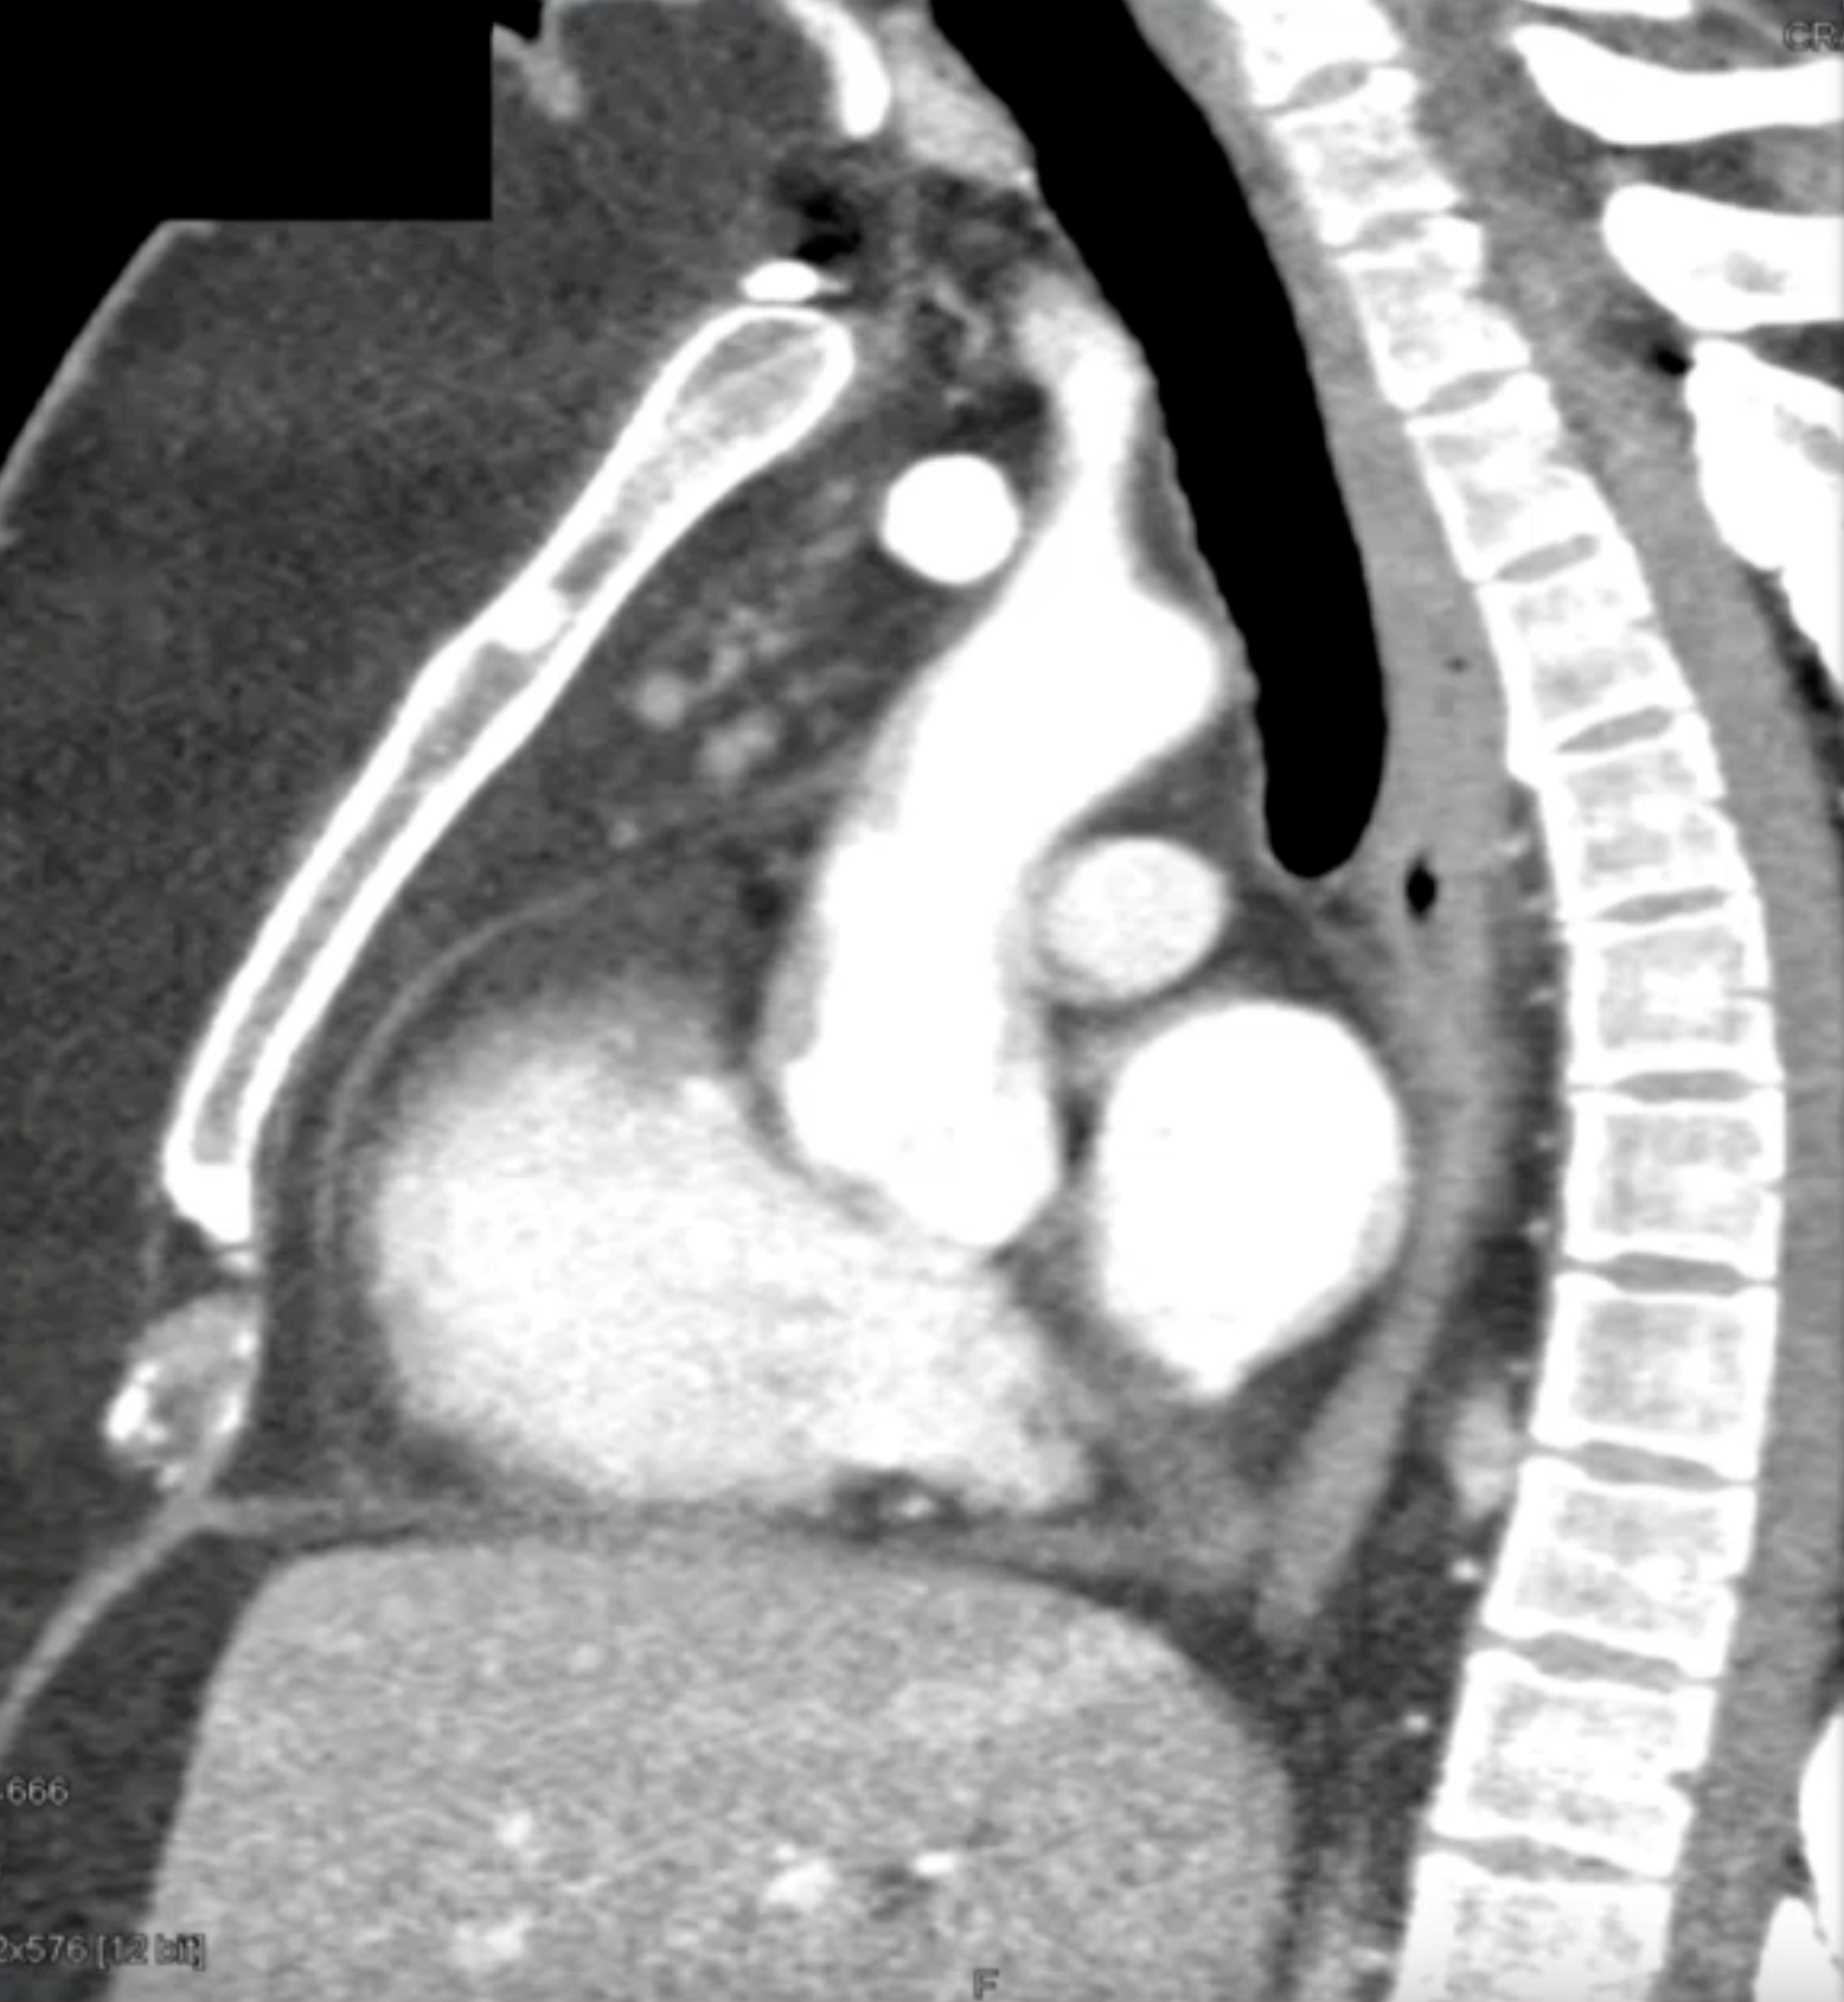

Thymolipoma